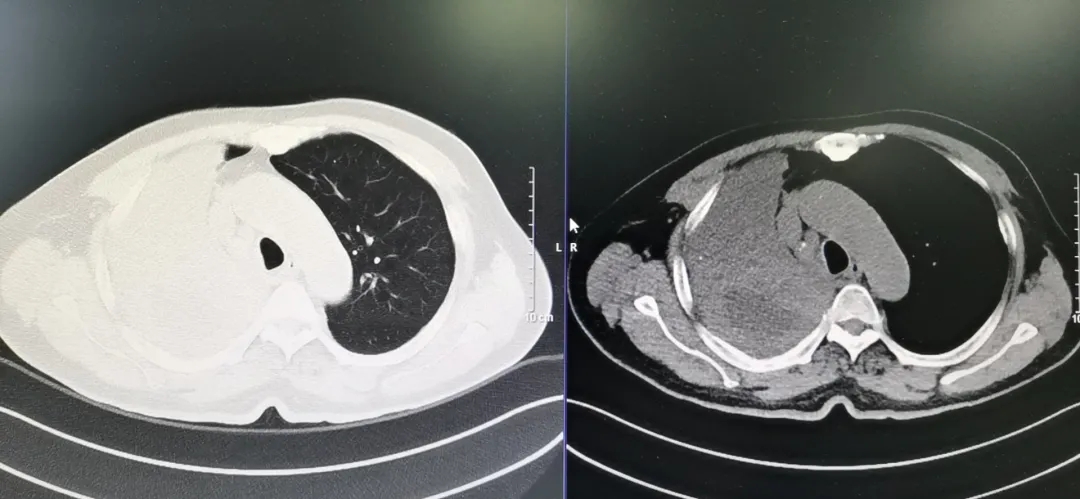

患者,男,71岁,以“反复咳嗽2年余,呼吸困难10余天”入住呼吸与危重症医学科。入院查体:呼吸稍促,R26次/分,入院后行胸部CT提示:右肺上叶实性肿块,考虑恶性肿瘤,中央型肺癌伴阻塞性不张、肺炎。

胸部CT

患者在行支气管镜下检查时发现“右主支气管重度狭窄;右主气管黏膜病变”。当即取右主气管黏膜活检,病理提示“鳞癌”。患者因严重气道梗阻,已经出现呼吸困难症状,韦庆主任通过评估后,决定通过支气管镜气道支架置入术,尽快解决患者的呼吸困难。但是患者年纪大,气道梗阻严重,术中随时可能因缺氧等情况引起严重并发症,呼吸内镜团队通过认真讨论,做出了充分的准备后,为患者实施经气管镜气管覆膜支架置入术。手术过程顺利,支架顺利置入,完美精准,一步到位。术后患者呼吸困难症状即刻缓解,效果明显。